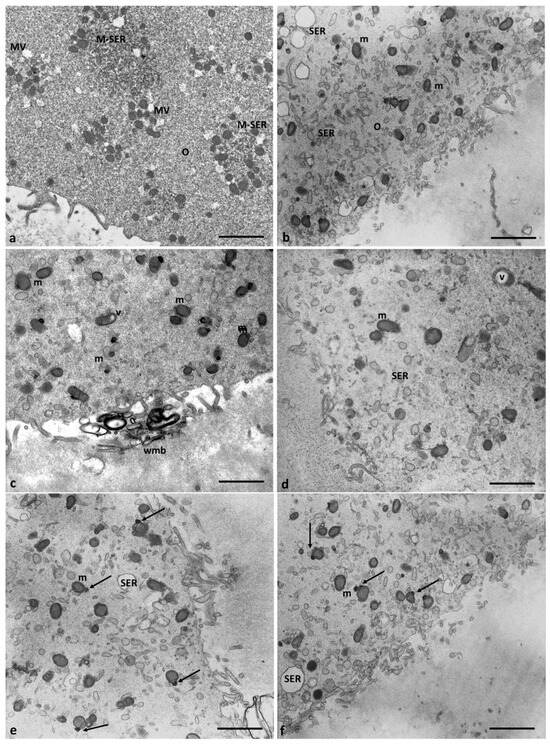

However, all the oocytes of Group 2 patients exhibit ultrastructural changes in some organelles. Figure 6 shows the presence of several large, communicating, dilated SER vesicles in the center of the ooplasm, with a secretory, moderately electrodense material in the lumen indicating endoplasmic reticulum stress leading to frank vacuolization. The presence of autophagosomes dispersed among the SER vesicles and large but scarce MV complexes sometimes showing interrupted membranes confirms possible metabolic cell suffering.

Figure 6.

Evidence of endoplasmic reticulum stress in the oocytes of Group 2 patients. (a,b) Large, communicating dilated SER vesicles occur in the center of cytoplasm and (c,d) details at high magnification of scarce and large MV complexes and autophagosome (A) between SER vesicles that appear more numerous. Bar = 2 µm (a); Bar = 1 µm (b); Bar = 800 nm (c,d).

In the oocytes of Group 2 patients, mitochondria were numerous and uniformly distributed. However, in association with the dilated endoplasmic reticulum, which was different from the control oocytes (Figure 7a), electrodense mitochondria with lapsed cristae and a denser matrix, and smaller, pycnotic, and electrodense ones were present in the cortical area (Figure 7b–d). Most mitochondria, dispersed in the cytoplasm and separated from SER vesicles, had a mitochondrial matrix containing prominent electron-dense granules (Figure 7e,f, arrows). Moreover, some vacuolated mitochondria have been observed.

Figure 7.

Mitochondria ultrastructural changes in oocytes of Group 2 patients. (a) Mitochondria of the oocytes of Group 1 patients are organized in M-SER aggregates and MV complexes. (b–d) Mitochondria of the oocytes of Group 2 patients appear isolated, are not associated with SER vesicles, and are both swollen with lapsed cristae and smaller/pycnotic; vacuolated (v) mitochondria are also present. (e,f). Note the mitochondrial matrix with prominent electron-dense granules (arrows). Bar = 1 µm.